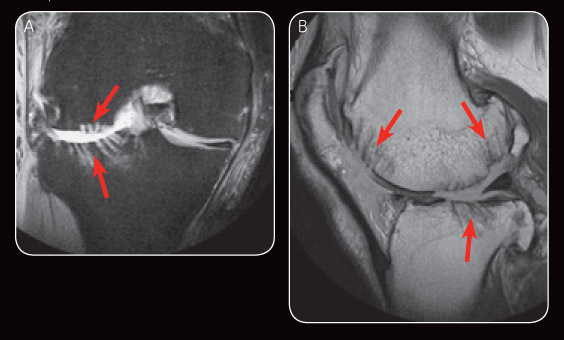

Fig. 2 Early post-operative MR images: PDFS (A) illustrates subchondral drilling at the lateral femoral condyle and lateral tibial plateau. Sagital PD (B) shows areas of subchondral drilling.